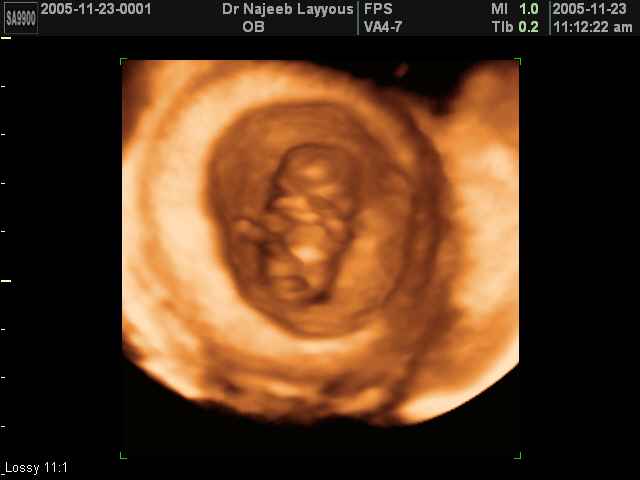

3D First Trimester Ultrasound Scan Photos